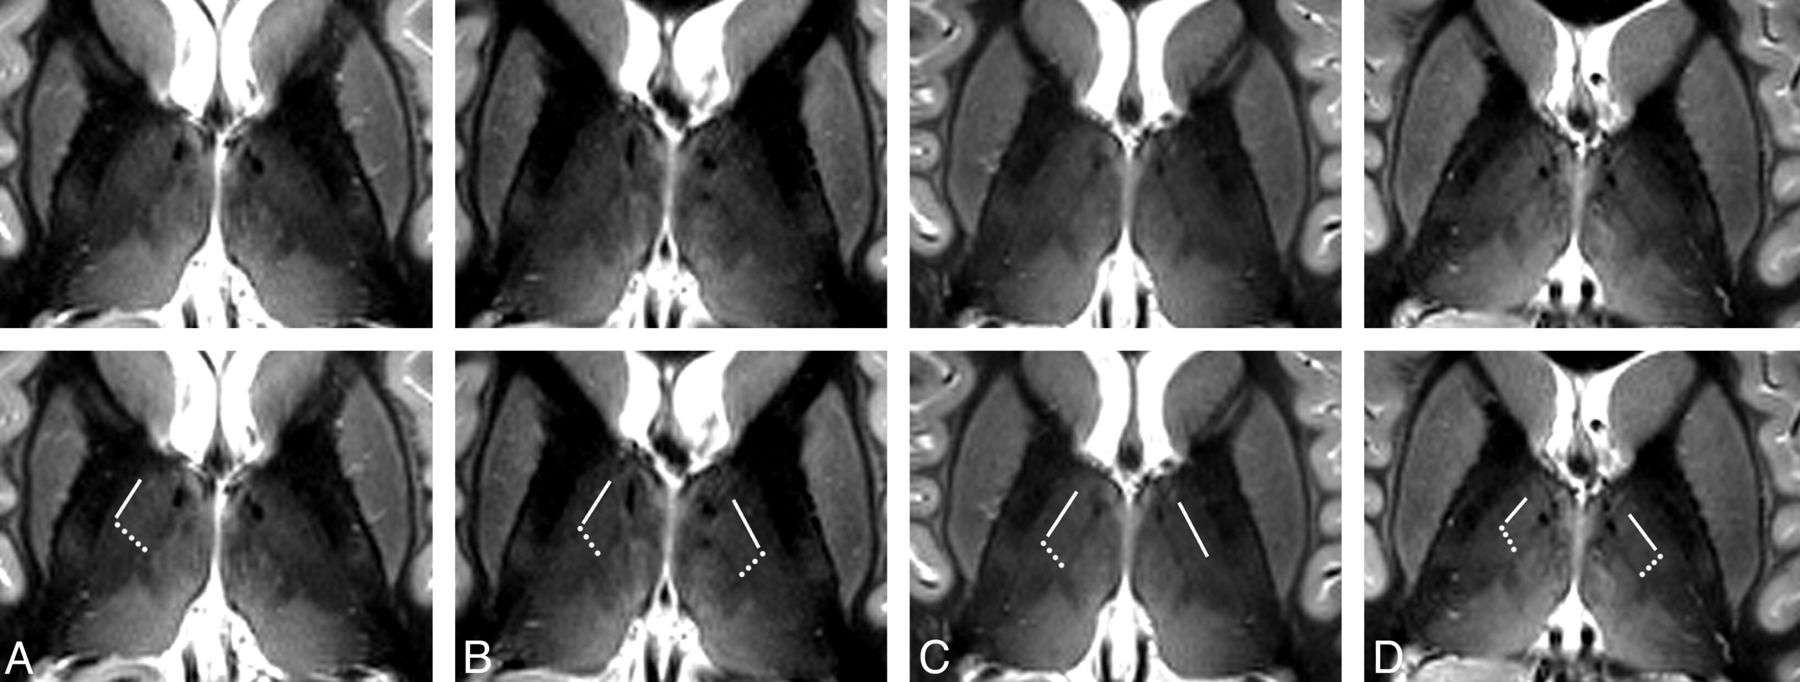

The images in Fig 2 show axial sections through the thalamus 16, 13, 10, and 7 mm dorsal to the ACPC plane of the same subject as depicted in Fig 1 (recorded during a different session). The La.m can be clearly identified in the dorsal 3 sections, but it looks faded and weakly contoured in the most ventral section in the right image of Fig 2. The most probable reasons are intralaminar cell clusters and the larger lateromedial width of this lamina at more ventral levels.23 Only in the section 10 mm dorsal to the ACPC plane does the boundary between the D.o.i and Z.im.i appear as a well-defined edge. In the neighboring sections, gradual signal-intensity transitions, in an anteroposterior direction, of the lateral thalamus are discernible. These diffuse changes in signal intensity hamper the demarcation of distinct thalamic structures. At the present stage, we cannot definitively state whether partial voluming is the main reason or whether a smooth transition of the MR relevant tissue properties of neighboring thalamic compartments impedes the formation of a distinct boundary. Images of the same anatomic location for the 4 other measured subjects are shown in Fig 3. At the reduced in-plane resolution of 0.72 mm2 and a section thickness of 2 mm, the boundary between the D.o.i and Z.im.i, the boundary between the D.o.i and D.o.e, and the La.m can be assigned in a reliable manner in almost all cases. The subject in Fig 3A seems to have a relatively slim D.o.e. Also of note is the rather diffuse appearance of the D.o.i/Z.im.i boundary in the left hemisphere in Fig 3A, -C.

Axial MR images of different subjects. Axial sections through the thalamus in a plane approximately 10 mm dorsal to the ACPC plane of 4 different subjects (A–D) acquired with an IR-TSE sequence (TI = 500 ms and 0.72 × 2 mm3 resolution). In the bottom row, which is identical to the top row, lines mark the border between the anatomic subfields D.o.i and D.o.e and dotted lines show the border between the subfields D.o.i and Z.im.i. In the left hemispheres in A and C, diffuse-appearing boundaries are not marked. At this coarser in-plane resolution, the L.am appears more blurred than in Figs 1 and 2. Some images show blood flow artifacts in the medial thalamus (see also Fig 5).